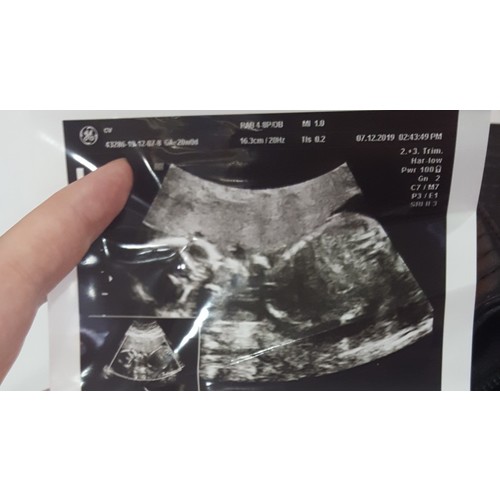

Als je kindje niet goed lag kan ze het hartje niet goed beoordelen, wat wel belangrijk is. Ze moet namelijk kunnen zien of de hart Kamers goed ontwikkeld zijn, de aorta goed zit, of de bloedtoevoer en afvoer goed is, of er geen gat zit tussen de kamers ect. Het is niet heel ongebruikelijk om nog een keer terug te moeten komen voor een echo omdat ze niet alles hebben kunnen zien. Bij hart afwijkingen komen ze er liever nu achter, zodat ze er nu - later in de zwangerschap al wat aan kunnen doen, of waar ze tijdens de bevalling al rekening mee moeten gaan houden als er iets aan de hand is. Ze doen dit echt niet zomaar om extra geld eruit te kunnen slaan.

Bij deze zwangerschap 2 keer terug geweest omdat de kleine niet goed lag waardoor ze het gezicht niet konden zien, en dus ook niet konden zien of de oogkassen goed zijn ontwikkeld, en of het gehemelte gesloten is

nee het gaat niet om her feit dat ik terug moet komen. Zij stuurt mij naar een zhuis met slechte aparatuur. Zij werkt zelf in een luxe zhuis om.zo uit te leggen in turkije heb je verschillende kwaliteit zhuizen. Devlet betaal je niet voor maar de aparatuur en dokters daar zijn niet goed . Wij gaan naar ozel betaal je veel voor maar aparatuur is 10 x beter . Zij stuurt mij naar haar man die met slechter aparatuur werkt in University zhuis daar betaal je ook . Dus aan mn mans vrienden gevraagt en gaven allemaal aan dat ik naar n andere dokter moet maar mijn vraag was meer van of iemand ook heeft gehad dat hartj3 eerst 5 sec max wat langzamer ging maar daarna gewoon lekker snel .. iedergeval bedankt voor je reactie